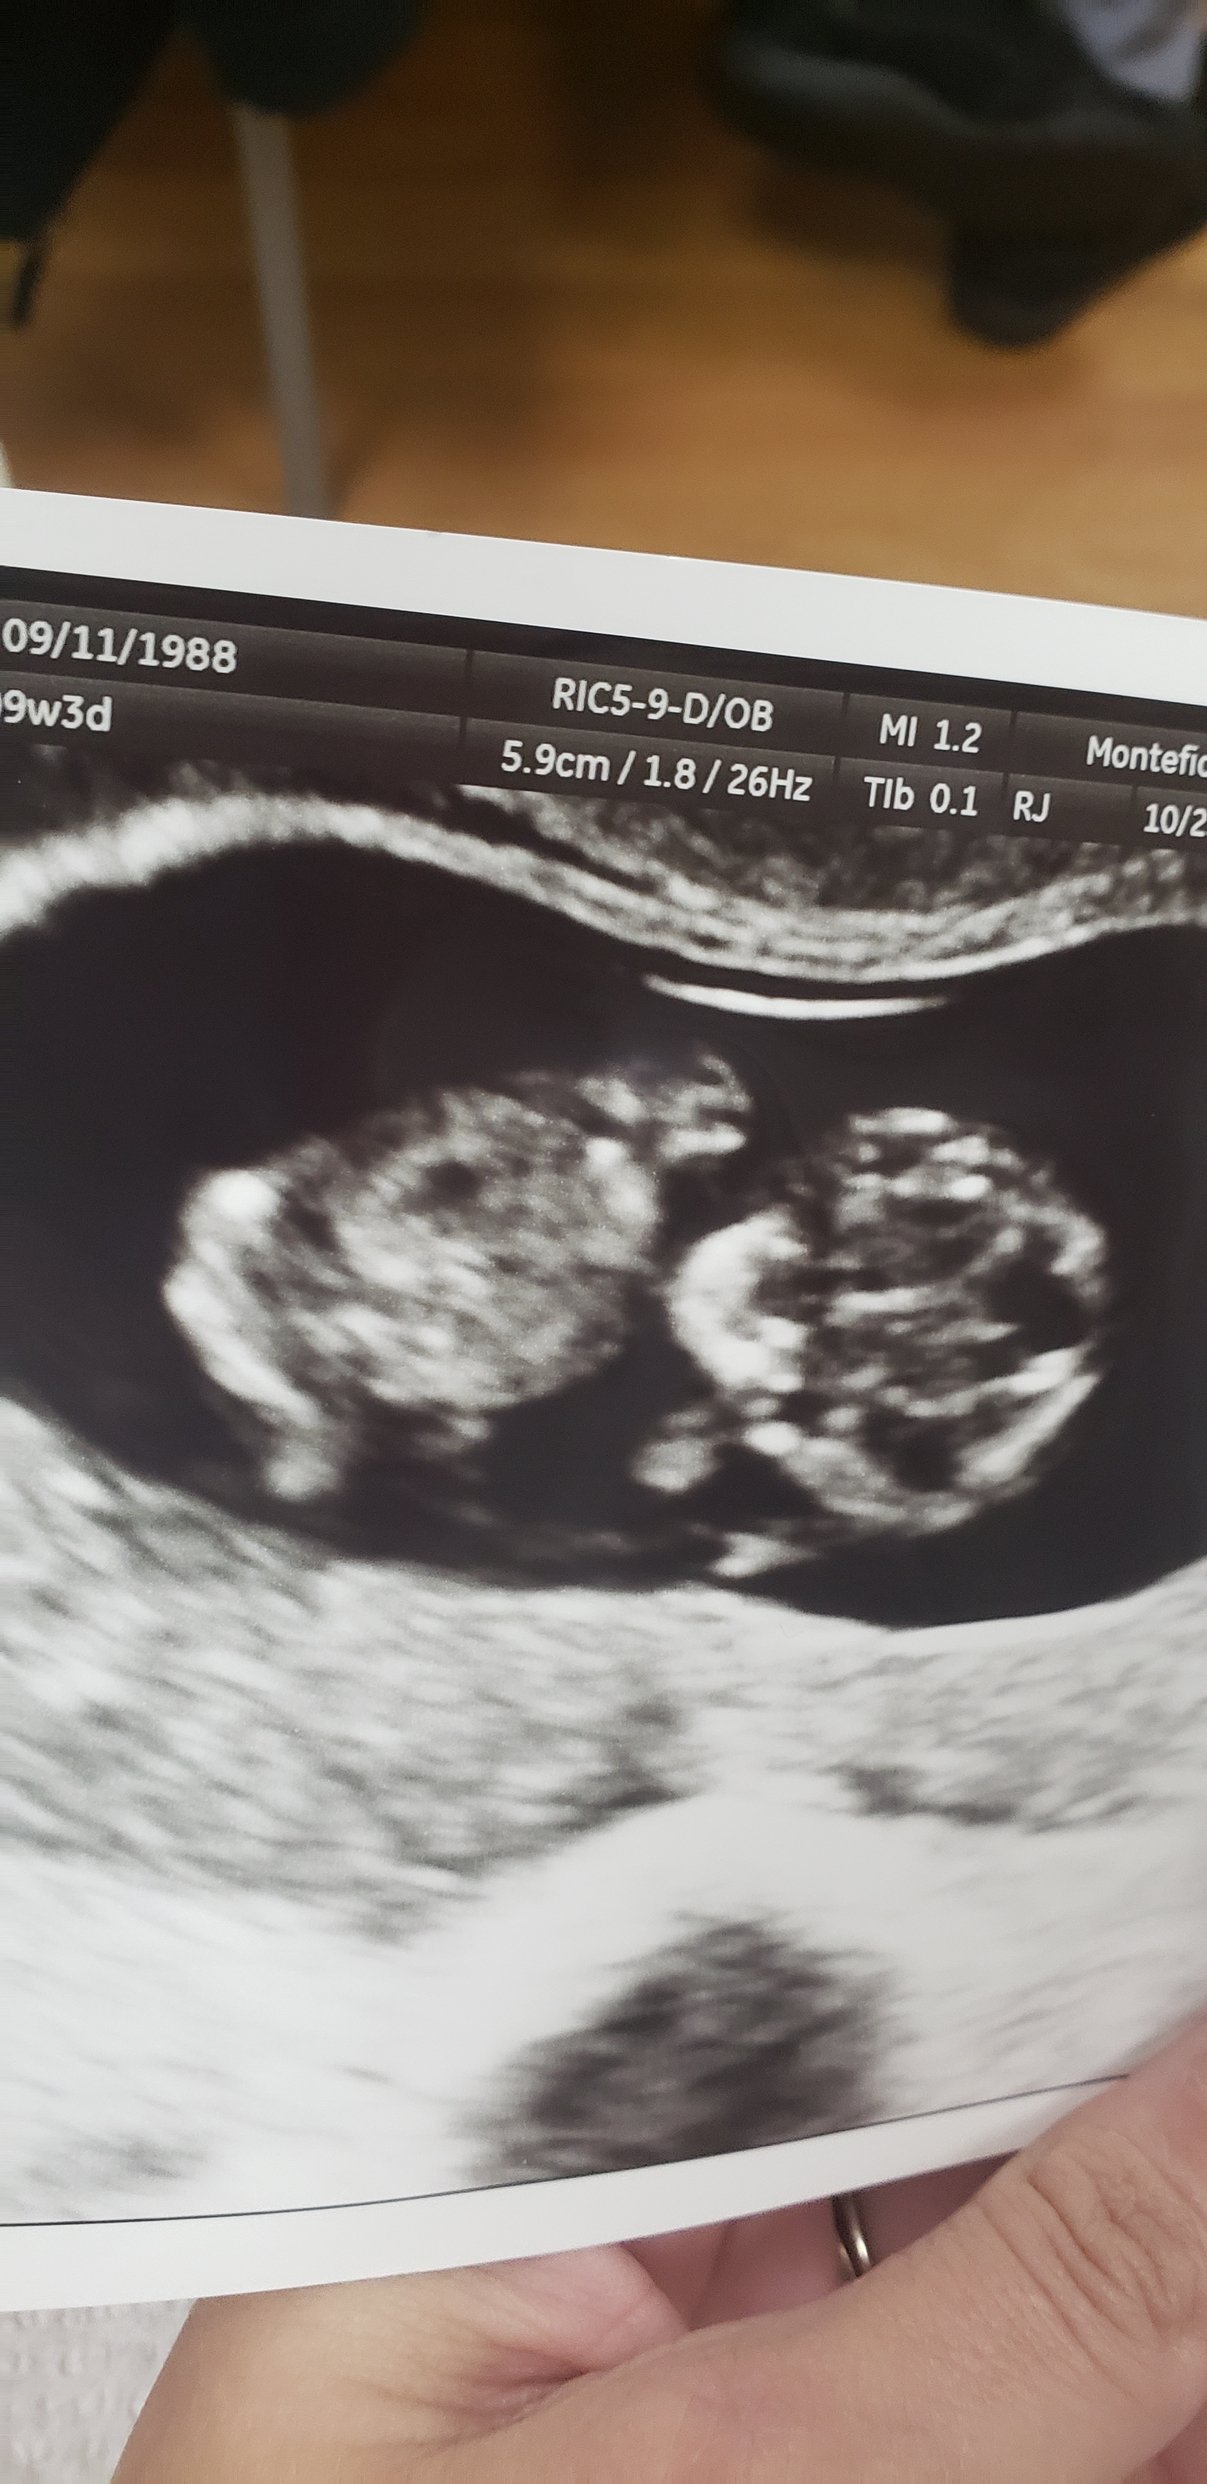

11 weeks makes a huge difference! I could see little peanut rolling around, waving it’s arms and legs, and it’s face even looked human!! I totally cried. I have my NIPT appointment in two weeks and can not wait to get another ultrasound!!!